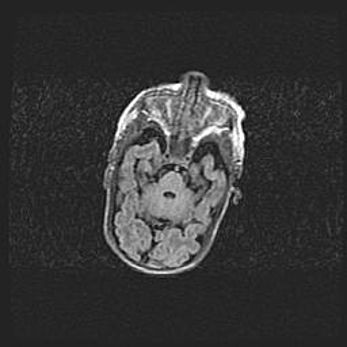

Сообщающаяся гидроцефалия. Кистозная энцефаломаляция головного мозга.

Возраст: 3 месяца 4 дня

Вес: 3100 г

Пол: женский

Окружность головы: 34 см

Срок гестации: 31 неделя

Кистозная энцефаломаляция головного мозга - одна из форм поражения головного мозга в детском возрасте. Характеризуется возникновением множественных и распространённых кист в коре, белом веществе и подкорковых образованиях головного мозга у плодов, новорождённых и детей раннего возраста. Развитие кистозной энцефаломаляции связано с внутриутробной асфиксией и гипотонией, родовой травмой, тромбозом синусов, пороками развития сосудов, инфекциями, сепсисом и другими причинами. Наиболее значимые инфекционные агенты: вирусы простого герпеса, цитомегалии, краснухи, токсоплазмы, энтеробактерии, золотистый стафилококк и другие.